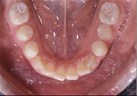

Dental Casts

right buccal frontal left buccal upper mandibular

Right Buccal View Frontal View Left Buccal View Maxillary View Mandibular View